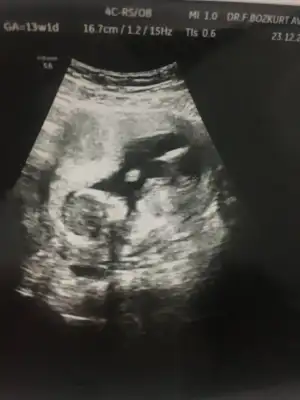

dr soylemeden siz gorun genital nub teorisi ( bebegin cinsiyeti)

Merhabalar biraz büyüdük tekrar geldik 12+2 karından bakıldı bi tahmininiz varmı 😊